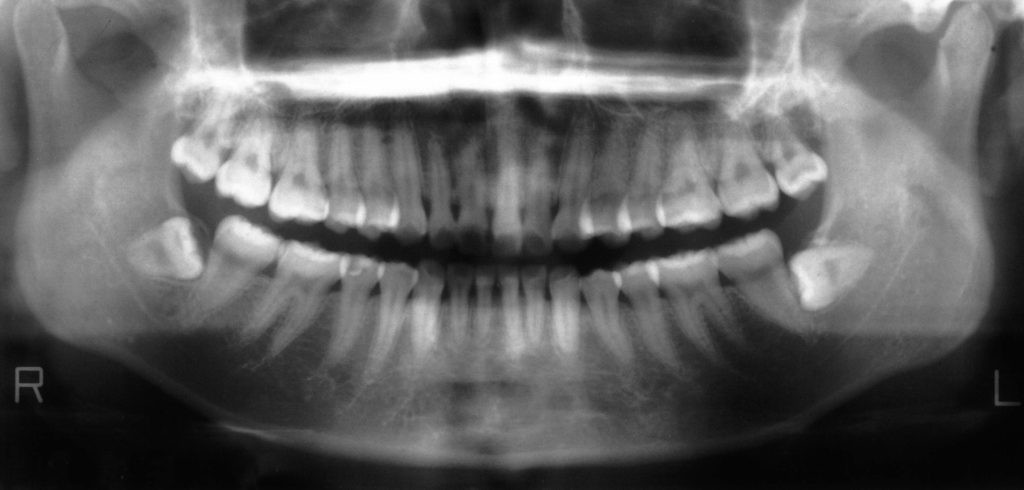

① パノラマレントゲン写真

顎の骨を含めてお口全体を撮影するレントゲンです。

吉本歯科医院では初診の患者さんに必ず撮影しています。

実際のパノラマレントゲンの見方

白く映っている部分は「歯」や「骨」です。

パノラマレントゲンでは、鼻の空洞・顎関節・下顎全体まで確認できます。

たとえば、下顎の左右に横向きで埋まっている親知らず(8番)を見ることができます。

私は患者さんに説明するとき、よく「畑に大根が植わっているイメージ」とお伝えしています。

黄色い部分が畑(土=骨)、白い大根が歯です。

親知らずは隣の歯を圧迫し、どんどん食いつぶしていきます。

放置すると隣の歯もダメージを受けるのです。